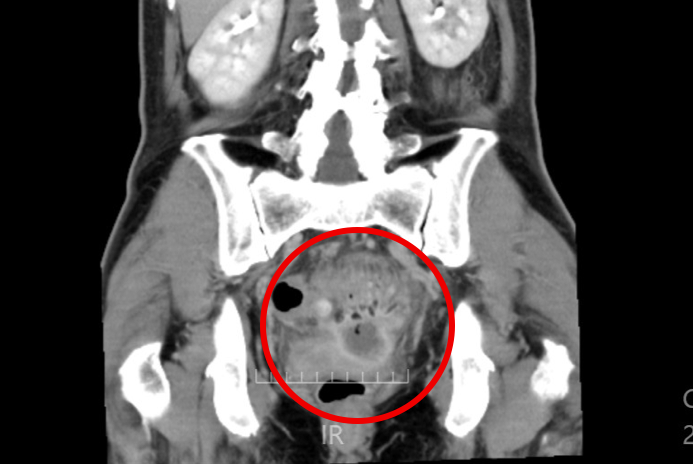

別の高さの画像を見ると、白い壁に囲まれた膿のたまりが確認できます。ちょうど子宮、S状結腸、直腸という臓器に囲まれています。

正面から見ても同じような膿のたまりが確認できます。